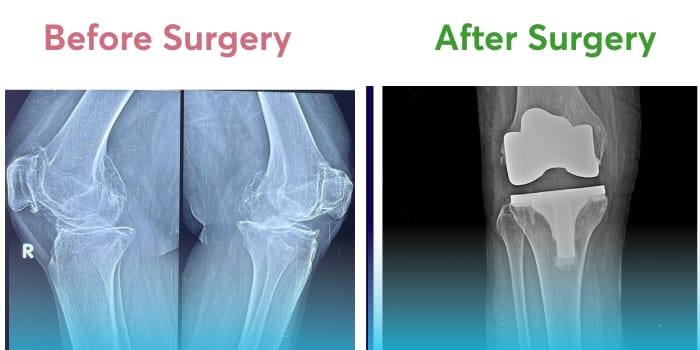

The knee joint is the biggest in the human body, connecting the thigh-bone or femur to the Tibia or shin-bone in the lower leg. The knee joint is a hinge-type synovial joint and one of the most complex joints in the body. It is a network of ligaments and muscles that keeps the body sturdy while standing or moving around. The most important components of the knee joint are the Meniscus and other ligaments like PCL, ACL, MCL, and LCL.